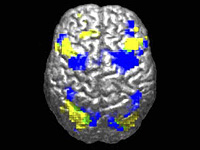

Новая модель ИИ может расшифровывать МРТ головного мозга за секунды

По данным исследования, ученые из Мичиганского университета создали ИИ-модель, способную анализировать МРТ мозга и выдавать диагностическое заключение за считанные секунды. Система определяла неврологические заболевания с точностью до 97,5% и оценивала, насколько срочно пациенту требуется медицинская помощь. По мнению авторов работы, эта технология может существенно изменить подход к нейровизуализации в американских медицинских учреждениях. Результаты исследования опубликованы в журнале Nature Biomedical Engineering.

При анализе более чем 50 радиологических диагнозов, связанных с основными неврологическими заболеваниями, модель Prima показала более высокую диагностическую точность по сравнению с другими современными ИИ-системами. Она также эффективно определяла, какие случаи требуют первоочередного внимания. По словам исследователей, при таких состояниях, как внутримозговые кровоизлияния или инсульты, где счет идет на минуты, Prima способна автоматически уведомлять медперсонал, чтобы ускорить оказание помощи.

Система также подсказывает, какого узкопрофильного специалиста следует привлечь – например, невролога по инсультам или нейрохирурга. Эта информация становится доступной сразу после завершения визуализационного обследования. Prima – это мультимодальная ИИ-система, которая умеет одновременно работать с изображениями, видео и текстом в реальном времени. Хотя ИИ уже применяли для анализа МРТ и других методов нейровизуализации, подход Prima отличается от предыдущих разработок. Ранее модели обучали на специально отобранных наборах МРТ-данных для решения узких задач – например, поиска очагов поражения или оценки риска деменции.

Команда пошла другим путем: Prima обучили на полном архиве МРТ Медицинского центра Мичиганского университета – это более 200 000 исследований и около 5,6 миллиона последовательностей, накопленных с начала цифровой эпохи в радиологии. Кроме самих снимков, в модель добавили клинические данные пациентов и информацию о том, почему врач назначил визуализационное исследование.